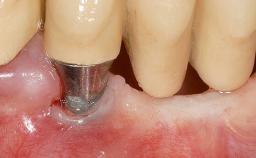

Early Implant Placement, Contour Augmentation, and Autologous Connective-Tissue Graft Using a Tunneling Technique to Replace an Upper Incisor with Generalized Gingival Recession

Variations in soft-tissue volume, evidenced either by an overabundance (Evian and coworkers 1993; Levine and McGuire1997; Dolt and Robbins 1997) or by a deficiency of soft or hard tissue can complicate implant-supported rehabilitations in the esthetic zone (Lorenzana 2008; Lorenzana and coworkers 2009). The present case illustrates the replacement of a failing upper left lateral incisor complicated by generalized severe gingival recession in the esthetic zone.